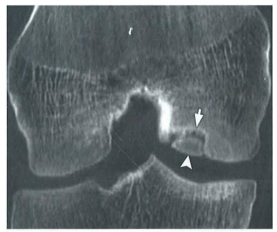

Tomografia do joelho abaixo demonstra falha óssea na face lateral do côndilo femoral medial (apontada pelas setas). O diagnóstico

CORRETO

é:

Osteocondrite dissecante.